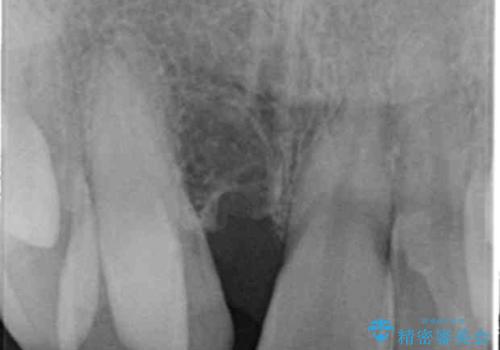

正中過剰埋伏歯で生じた前歯の審美障害 矯正治療での改善

当初他院では、抜歯を行いセラミックブリッジを提案されていましたが、他の方法はないかと総合歯科治療を行う当院へと相談来院されました。

「時間がかかっても良いので、できれば歯を抜かずに矯正治療で治したい。」という強い希望があったので、矯正治療で歯並び・審美性の改善を計画します。